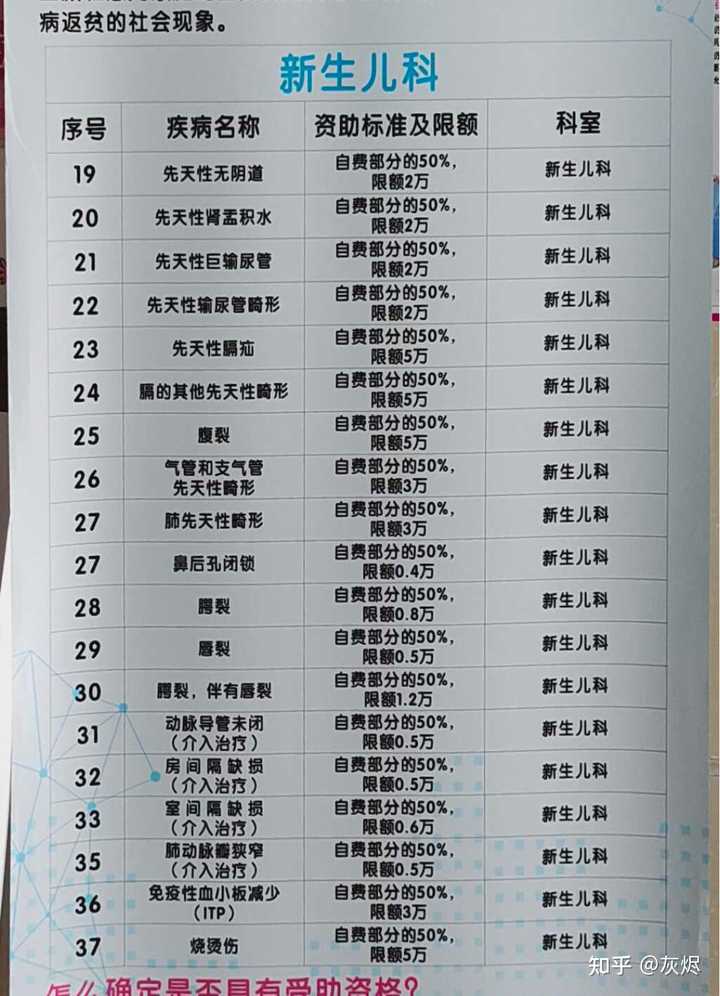

1929年10月汪精卫才从法国回香港,中医骗那是张嘴就谎啊,还张嘴就汪精卫掌实权,汪精卫1929年10月回来是支持第二次蒋桂战争干老蒋的,他还掌实权。 中医骗的特点就是张嘴就喷谎。主打一个我虽然小学3年级文化,但是够我骗文盲。 1929年,弗莱明刚刚发明抗生素,还只是实验室与论文,这就跑中国来了? 1929年,面对细菌性痢疾,西医就是没有办法治疗,所以就说治不了。1929年弗莱明虽然已经发明青霉素,但是产量感人,当时第一次使用对一个受伤感染的警察,非常有效,但是手中的一点青霉素用完了,于是警察还是shi了。 所以,西医诚实的说,没有办法治疗。 而诚实,是一种多么宝贵的品质。 因为你诚实,你说出来:我不能治疗,那么,这个疾病,就有了解决了一半。 因为你以后,所有的西医,西药,医疗器械从业者,都会想尽办法去攻克这个疾病。 而多少的绝症,曾经的绝症,因为西医的诚实,而最终研究出了真正治疗办法。 例如1921年的胰岛素。 例如1929年的青霉素。 例如1998年的伟哥。 例如2006年的HPV疫苗。 你没有。 3、西医不仅是个自然科学,他还是个管理秩序。 没有人敢保证每个西医从业者都会履行自己的诺言,所以西医除了希波克拉底誓言,还双管齐下,有一套完整的制度。 1)、一人为私,二人为公。西医的任何重大治疗与决策都是多人完成。 手术有术前评估,有术前讨论。 化验师管理体系是单独的。检查技师管理体系是单独的。甚至护士也是单独独立的。护士只是执行医生的医嘱,只是工作关系,不是上下级。护士的管理也是独立的,不归医生管理。麻醉师的管理也是独立的。 而这么多的独立,就是垂直管理,在根子上就切断医生自己一手遮天的可能。 2)、完善的文档记录。 住院病例保存30年。 住院病例需要上级医生签名。需要三级签名。修改需要红笔。 交病案后就归病案室,医生是要不回来了的。因为病案室也是独立的。 出院一定会给出院小结。需要全病历的也可以,掏复印费去病案室复印,所有的医院都允许。 所以很多中医骗张嘴就是他啥病西医看不好去找中医一看就好了,我就让他发出院小结,结果没有一个发的。我不要你隐私,你把你个人隐私涂掉,我就要病案。没有,全闪了。 等等。 在网上随便找点: |

一份最简单的住院小结,而且是格式化的,入诊、出诊、入情、治经、出情、医嘱,是格式化的,医生根本就删不掉。 送礼物 还没有人送礼物,鼓励一下作者吧 |